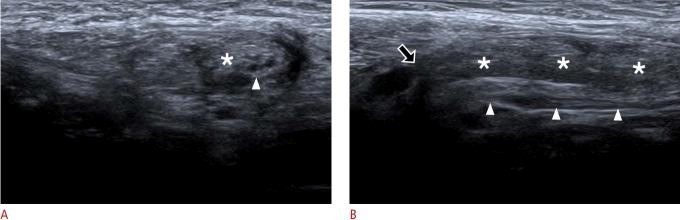

Prinsip ini dapat diekstrapolasi secara langsung ke diagnosis banding hidrokel. Salah satu diagnosis banding utama adalah hernia inguinalis. Hernia inguinalis yang berisi omentum atau usus mungkin hanya menjadi jelas atau dapat dikarakterisasi secara definitif selama manuver dinamis seperti Valsalva, yang meningkatkan tekanan intra-abdomen dan memaksa isi hernia masuk ke dalam kantung skrotum.

Oleh karena itu, pemeriksaan USG skrotum "standar" yang mengabaikan manuver dinamis saat mengevaluasi pembengkakan skrotum adalah pemeriksaan yang tidak lengkap dan berisiko salah mendiagnosis hernia sebagai hidrokel sederhana atau kompleks. Ini mengangkat diskusi dari sekadar daftar teknik menjadi komentar kritis tentang praktik terbaik, dan menekankan bahwa jika hernia ada dalam diagnosis banding, pencitraan dinamis sangat penting untuk diagnosis yang akurat.

Gambar 2. USG pasien dengan Hernia inguinalis. Tampak hernial sac yang didalamnya berisi peritoneal fat dan usus

Mengidentifikasi Isi Hernia: Fitur definitif dari hernia adalah adanya isi intra-abdomen di dalam kantung skrotum. Ini bisa berupa omentum (yang tampak sebagai lemak hiperekhoik), atau lengkung usus (yang memiliki penampilan berlapis yang khas).

Pencitraan Dinamis Sangat Penting: Tanda yang paling dapat diandalkan adalah visualisasi peristaltik secara real-time di dalam lengkung usus yang mengalami herniasi. Manuver Valsalva atau batuk dapat digunakan untuk memprovokasi hernia, menunjukkan pergerakan isi melalui kanalis inguinalis dan peningkatan ukuran kantung hernia.

Komplikasi: Ultrasonografi juga dapat mengidentifikasi tanda-tanda inkarserasi (hernia yang terjepit dan tidak dapat direduksi), seperti tidak dapat direduksinya isi hernia dengan tekanan lembut, adanya cairan bebas di dalam kantung hernia, dan penebalan dinding usus.